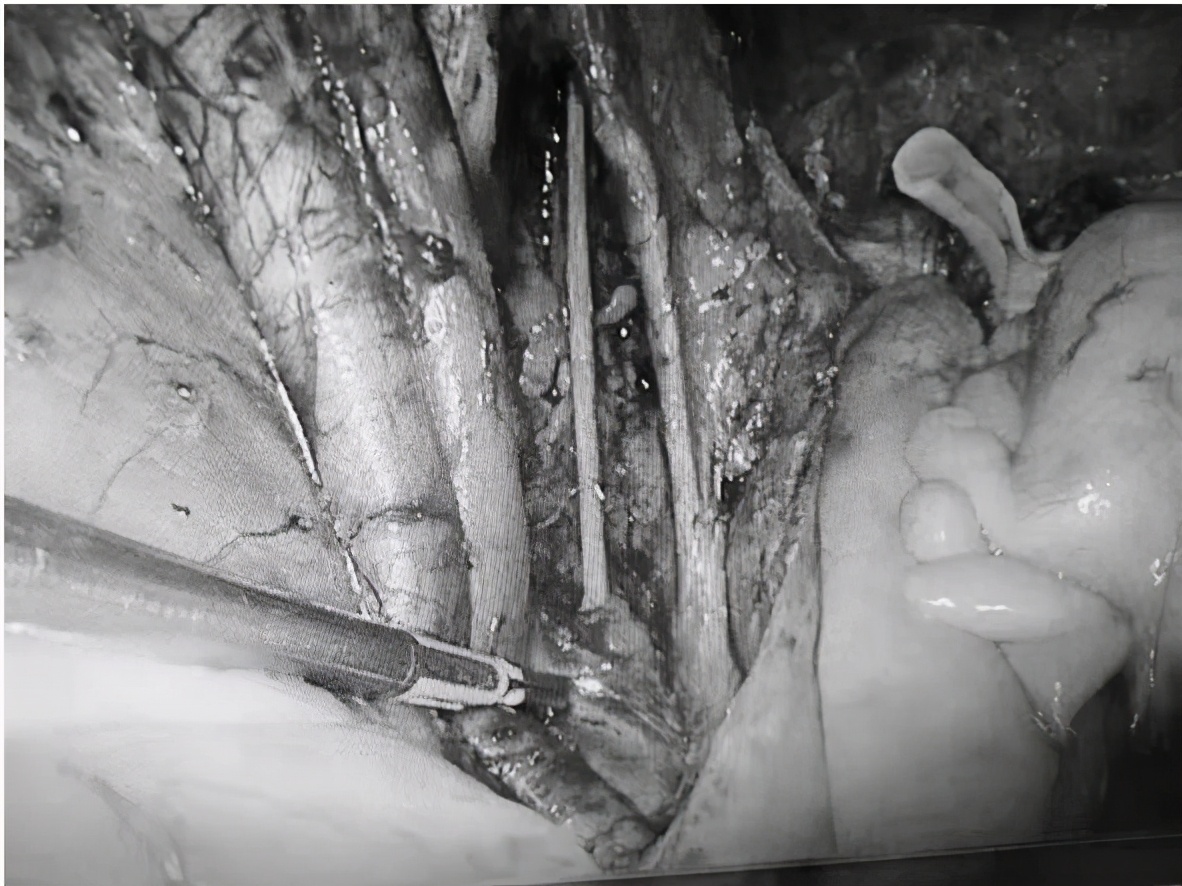

患者既往高血压3级、2型糖尿病,空腹血糖最高达16.4mmol/l,餐后血糖最高达25.6mmol/l;肝功能显示两项酶均高于正常值三倍以上,两项蛋白也均异常,腹部彩超提示脂肪肝;下腹部MRI显示子宫峡部内膜明显不规则增厚,符合子宫内膜癌Ia期表现,盆腔、双侧髂血管旁及腹股沟区多发小淋巴结影。随后积极请相关科室会诊,经过妇科、内分泌科、消化科积极联合治疗后,空腹血糖控制在4.3-8.3mmol/l之间,餐后2小时血糖控制在8.2-9.7mmol/l之间,肝功能大致正常,血压、血糖均达到手术安全范围。遂决定对患者行 腹腔镜下 子宫内膜癌全面分期手术:即 筋膜外全子宫切除术+双侧附件切除术+盆腔淋巴结清扫术 。

在经过术前充分的手术准备和术中麻醉医师的严密监护下,历时近7个小时,这台恶性肿瘤手术按步骤成功完成,整个手术过程仅出血30ml。患者回病房后,医护人员密切观察生命体征、引流液颜色及量,术后3天撤除引流管,病理回报无淋巴结转移,双侧宫旁阴性。术后7天,患者顺利出院。